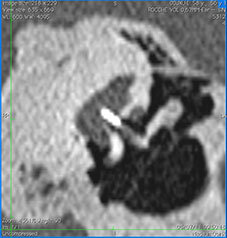

L’intervento viene effettuato con l’ausilio del microscopio operatorio, in anestesia generale o in anestesia locale con sedazione. Si pratica una incisione della pelle all’interno del condotto uditivo (quindi non visibile dall’esterno) e si solleva il lembo di pelle in continuità con la porzione posteriore della membrana timpanica. Per esporre l’incudine e la staffa è necessario spostare la chorda tympani (un sottile nervo che trasporta la sensibilità gustativa di una parte della lingua).

SI rimuovono quindi le branche (crura) della staffa e si pratica un foro nella platina. Quindi si applica una protesi (il titanio è il materiale da noi preferito) con gancio attorno all’incudine e pistone che attraversa il foro platinare; il gancio viene quindi fissato all’incudine.